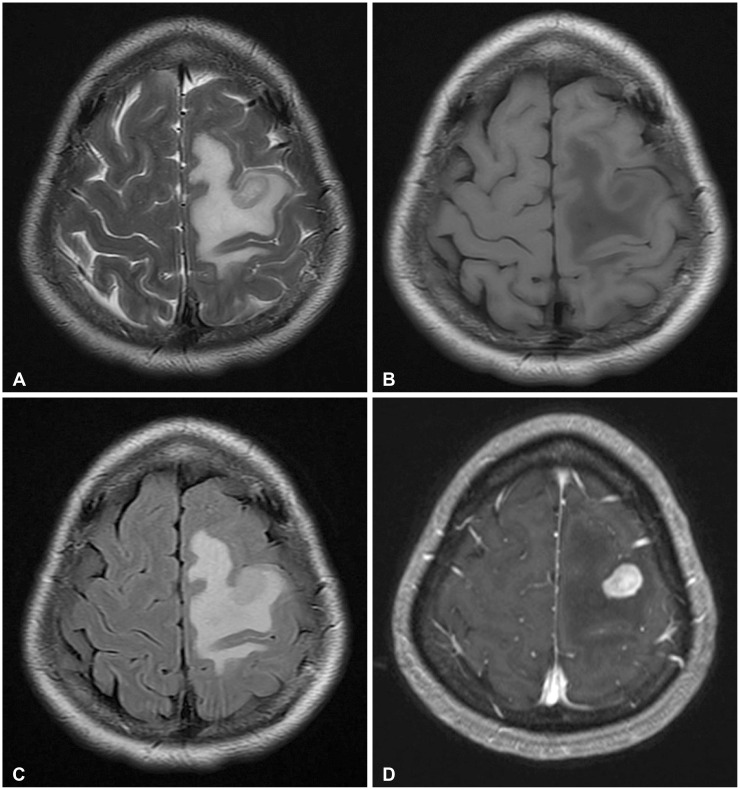

This paper discusses a rare case of a 49-year-old female diagnosed with a central nervous system-isolated neoplasm with histiocytic features, classified as histiocytic neoplasm, not otherwise specified (NOS). Despite comprehensive histopathological and genetic studies, accurately diagnosing the case proved challenging. Initial surgical findings and frozen biopsy suggested a low-grade glioma; however, subsequent immunohistochemistry and genetic analysis excluded known histiocytic subtypes such as ALK-positive histiocytosis and Erdheim-Chester disease. The patient's condition improved following occupational rehabilitation therapy for right upper motor weakness, as well as anticonvulsant and radiation therapy, and her neurological condition remains stable. This case underscores the diagnostic challenges of Histiocytic Neoplasms and the necessity for interdisciplinary collaboration and sophisticated diagnostic techniques.